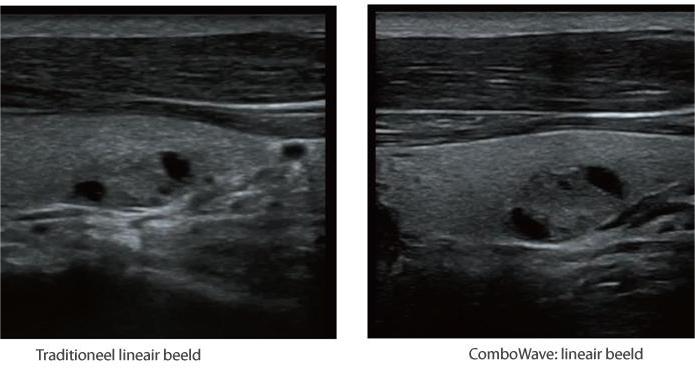

De DC-60 Exp met X-Insight is ontworpen op basis van diepgaand inzicht in klantbehoeften om hoge efficiëntie met nauwkeurige beeldverwerking te leveren, dankzij eXacte helderheid, eXceptionele intelligentie en eXcellente ervaring.